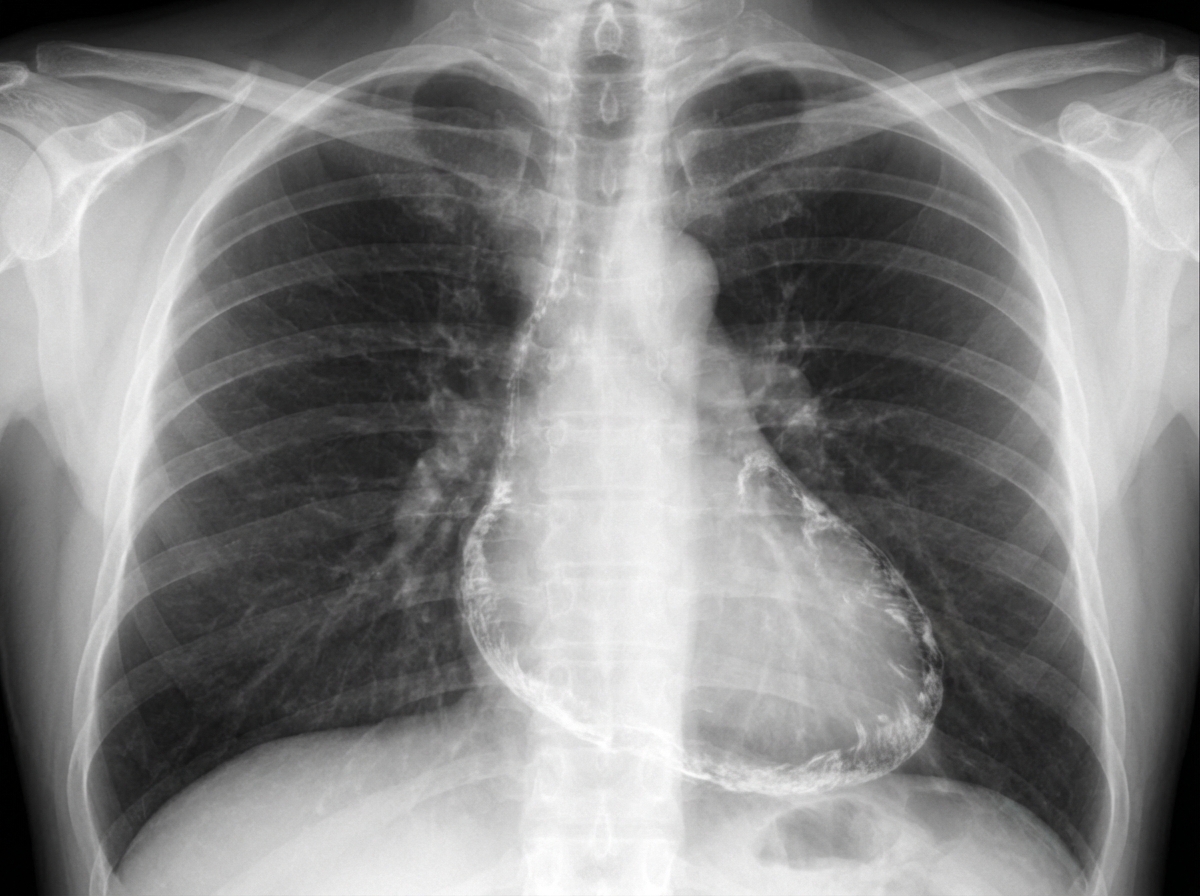

A 52-year-old man presents to the emergency department because of fatigue, abdominal distension, and swelling of both legs for the last 3 weeks. His wife says that he lost some weight recently. He has had type 2 diabetes mellitus for 12 years, for which he takes metformin and sitagliptin. He has a history of Hodgkin’s lymphoma which was successfully treated with mediastinal radiation 20 years ago. He does not smoke or drink alcohol. He has a family history of type 2 diabetes in his father and elder sister. Vital signs include a blood pressure of 100/70 mm Hg, a temperature of 36.9°C (98.4°F), and a regular radial pulse of 90/min. On physical examination, there is jugular venous distension, most prominently when the patient inhales. Bilateral ankle pitting edema is present, and his abdomen is distended with shifting dullness on percussion. An early diastolic knocking sound is audible on the chest. His chest X-ray is shown in the exhibit. Which of the following is the best treatment for this patient?